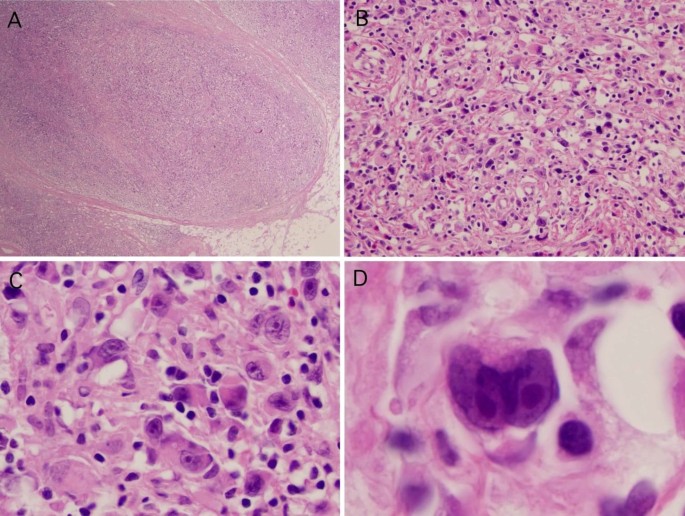

Микропрепараты: Лимфогранулематоз и Нодулярный Склероз

Раздел: Секреты мастерства